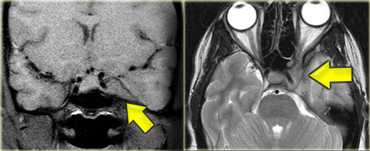

Schwannoma in CPA-region with typical features of an extraaxial tumor (T2WI) Schwannoma in CPA-region with typical features of an extraaxial tumor (T2WI)

The T2W-images show a schwannoma located in the cerebellopontine angle (CPA).

This case nicely demonstrates the typical signs of an extra-axial tumor.

There is a CSF cleft (yellow arrow).

The subarachnoid vessels that run on the surface of the brain are displaced by the lesion (blue arrow).

There is gray matter between the lesion and the white matter (curved red arrow).

The subarachnoid space is widened because growth of an extra-axial lesion tends to push away the brain.

All these signs indicate that this is a typical extra-axial tumor.

In the region of the CPA 90% of the extra-axial tumors are schwannomas.